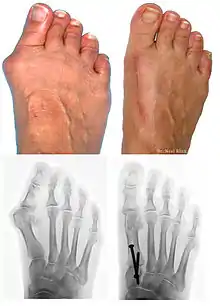

L’hallux valgus (HV, du latin hallus, gros orteil et valgus : « tourné en dehors »), souvent accompagné d'un « oignon » (callosité de la peau en regard de la déformation), est une déformation du pied correspondant à la déviation du premier métatarsien en varus (en dedans) et du gros orteil (hallux) en valgus (en dehors).

L'HV associe plusieurs déformations qui sont :

- un hallux abductus si M1P1 > 20° ;

- un metatarsus varus si M1M2 > 10° ;

Bilan radiographique

Le diagnostic est avant tout clinique, mais des radiographies sont indispensables pour mesurer la déformation et adapter la technique chirurgicale aux spécificités du patient. Les radiographies doivent être effectuées de façon rigoureuse : clichés d'avant-pied de face, profil, et 3/4, patient debout en charge. Ce dernier critère est indispensable car le squelette du pied adopte des positions dans l'espace qui diffèrent selon que le poids du corps repose ou non sur lui. C'est l'état du squelette debout en charge qui doit guider le geste chirurgical.